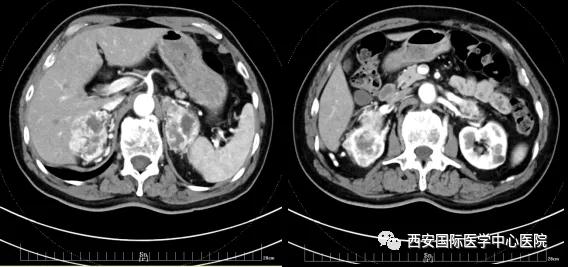

今年七十五歲的患者,來自陜西省商洛市,四月前因腰背部疼痛就診于當?shù)蒯t(yī)院,行CT檢查發(fā)現(xiàn)“右腎、雙側(cè)腎上腺占位,前縱膈淋巴結腫大,雙肺多發(fā)結節(jié)、胸椎骨質(zhì)破壞,考慮轉(zhuǎn)移瘤”。為進一步診斷治療,患者的兒子帶他來到西安某三甲醫(yī)院,查泌尿系CT提示“右腎占位性病變,多考慮腎癌,雙側(cè)腎上腺多發(fā)轉(zhuǎn)移灶,腹膜后多發(fā)腫大淋巴結”;行穿刺活檢提示“腎透明細胞癌”;并給予患者口服靶向藥物的治療方案。

自四月份至今,患者一直口服靶向藥物治療(阿昔替尼5mg 2次/日),期間無不良反應,目前腰背部疼痛癥狀也有所緩解,復查影像學資料提示瘤體較前縮小,腫瘤完整切除的可能性明顯提高;而且患者的兒子也是一名外科醫(yī)生,所以他更想為父親完成后續(xù)的手術治療。